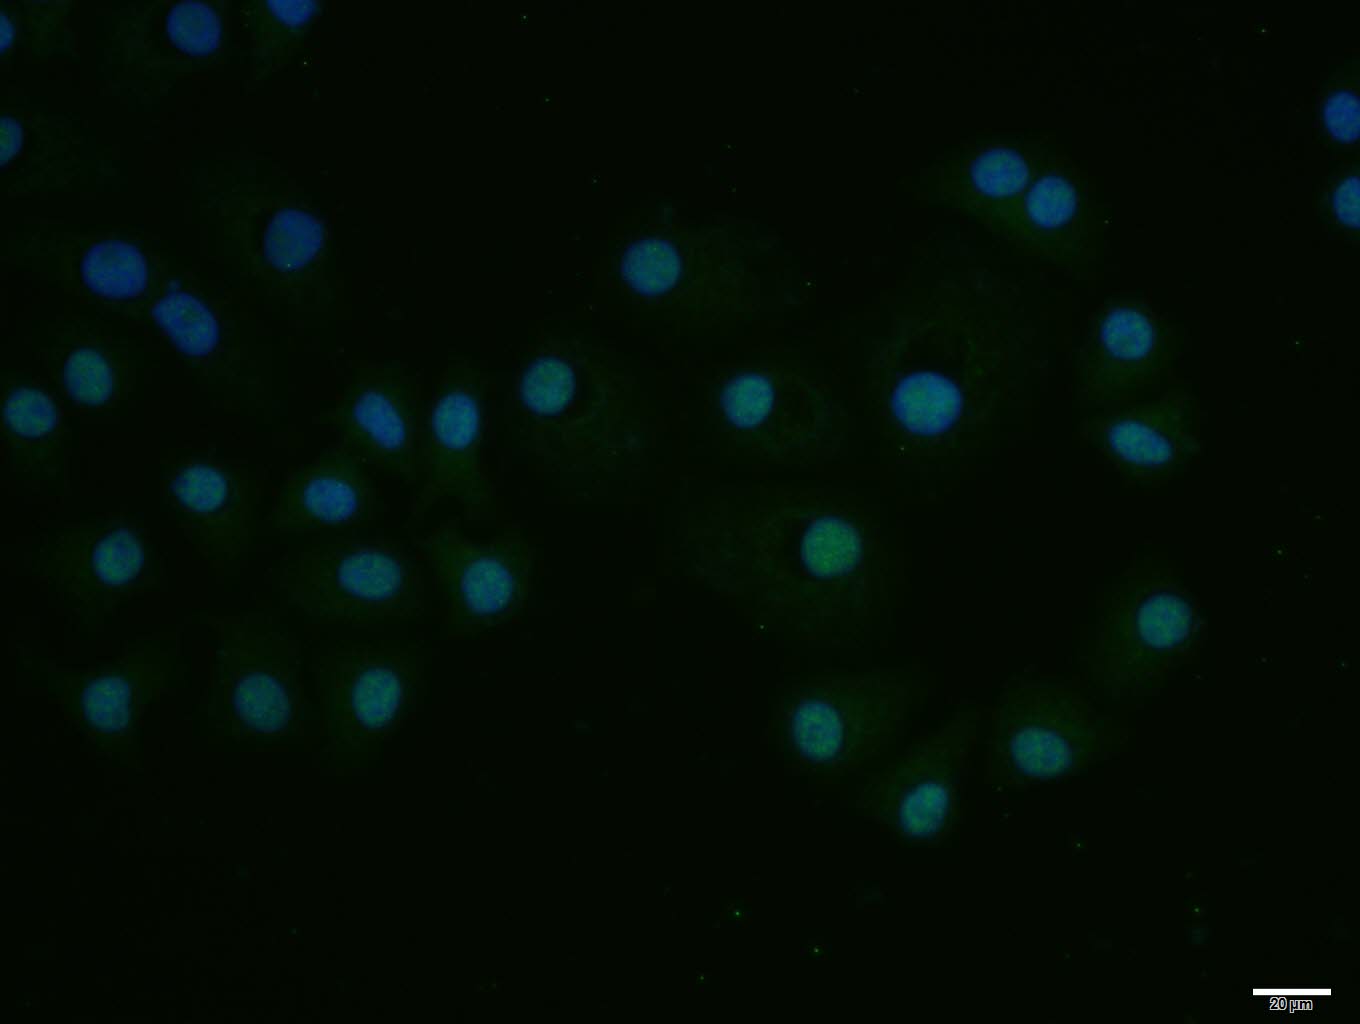

HepG2 cell; 4% Paraformaldehyde-fixed; Triton X-100 at room temperature for 20 min; Blocking buffer (normal goat serum, C-0005) at 37°C for 20 min; Antibody incubation with (E2F1) polyclonal Antibody, Unconjugated (bs-0599R) 1:100, 90 minutes at 37°C; followed by a conjugated Goat Anti-Rabbit IgG antibody at 37°C for 90 minutes, DAPI (blue, C02-04002) was used to stain the cell nuclei.